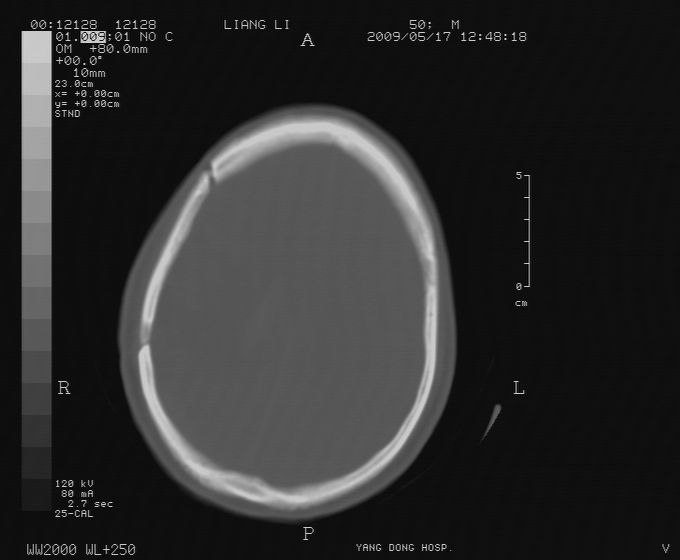

以下是引用zjzjr在2009-5-18 11:26:00的发言:[br]右颞枕叶及基底节区脑出血破入脑室系统,蛛网膜下腔出血,右枕顶部硬膜下血肿.颅骨及颅内低密度软化灶为血肿清除术后改变.

以下是引用随光逐影在2009-5-18 14:47:00的发言:[br]支持 右颞枕叶及基底节区脑出血破入脑室系统;蛛网膜下腔出血;右枕顶部及右侧天幕硬膜下血肿。右侧颅骨术后改变;颅内低密度软化灶为血肿清除术后改变。